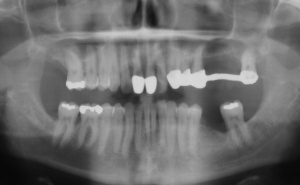

Aufgrund der parodontalen Destruktion, die letztlich erst mit dem intraoperativen Befund dreidimensional beurteilt werden konnte, mussten die Zähne 17, 26 und 27 als langfristig nicht erhaltungswürdig beurteilt werden. Da mit ihrem Verlust auch keine ausreichenden natürlichen Pfeiler mehr für einen definitiven festsitzenden Zahnersatz zur Verfügung standen, wurde eine implantatprothetische Versorgung mit zwei Implantaten in regio 15, 16 und drei Implantaten in regio 24, 25, und 26 geplant. Die Implantation und die entsprechenden präimplantologisch-augmentativen Maßnahmen wurde in der kieferchirurgischen Ambulanz (FU VIIb, Leiter Prof. Dr. Dr. K.O. Henkel) durchgeführt. Eine zwingende Indikation zur Versorgung der Freiendsituation ab 36 und der Schaltlücke bestand nicht, sodass in Übereinstimmung mit dem Patienten für den Unterkiefer kein Zahnersatz geplant und angefertigt wurde. Nach Wiedervorstellung im Oktober 2003 wurde die implantatprothetische Versorgung mit der Eingliederung der implantatgetragenen Kronen 15, 16, 24, 25, und 26 im November 2003 abgeschlossen. Mit der Eingliederung von Einzelkronen an 14, 13 und 23 im Februar 2004 wurde die Behandlung insgesamt abgeschlossen (s. Abb. 6). Die ursprünglich angedachte Extraktion der Molaren 17 und 28 wollte der Patient nicht mehr durchführen lassen.

e) Erhaltungstherapie:

Ab dem Februar 2004 wurde der Patient zur Sicherung des Behandlungserfolges in das in der FU VIIa – Zahnmedizin seit 1996 praktizierte Recallsystem aufgenommen. Diese Erhaltungstherapie beinhaltet die bereits erwähnten Maßnahmen der Unterstützenden Parodontitistherapie (UPT). Aufgrund dienstlicher Erfordernisse (u. a. immer wieder Seefahrten des Patienten) konnte der zunächst geplante Abstand von vier Monaten nicht immer eingehalten werden. Ein Abstand von ca. sechs Monaten konnte jedoch trotz der teilweise schwierigen Rahmenbedingungen realisiert werden. Am Zahn 44 kam es im Jahr 2006 zu einem Rezidiv, sodass an diesem Zahn im September 2006 eine Lappenoperation durchgeführt wurde. Der intraoperativ vorgefundene tiefe cirkuläre vertikale Defekt führte zur Einschätzung einer langfristig fraglichen Prognose von 44. Im Zuge der weiteren Erhaltungstherapie zeigten sich bis auf 44 die parodontalen und periimplantären Gewebe völlig unauffällig: So betrugen die Sondiertiefen bei entzündungsfreien klinischen Verhältnissen durchweg zwei bis drei Millimeter. Auch radiologisch zeigten sich keine Auffälligkeiten. Es gab keine Progredienz der ehemaligen parodontalen Erkrankung, die Osseointegration der Implantate zeigte keine Veränderungen (s. Abb. 7). Erhöhte Sondiertiefen verblieben lediglich am Zahn 44. Nachdem sich trotz regelmäßiger Nachsorge an 44 keine Entzündungsfreiheit der marginalen Gingiva erzielen ließ und die Zahnlockerung von 44 zunehmend stärker wurde, erfolgte im Jahre 2010 die Entfernung des Zahnes und der Ersatz durch eine implantatgetragene Krone (s. Abb. 8). Die Erhaltungstherapie wurde fortgeführt, Behandlungsmaßnahmen über die Inhalte der UPT hinaus waren bis zur Entlassung des Soldaten im Jahre 2012 nicht erforderlich. Der Patient blieb jedoch auch nach der Entlassung aus dem aktiven Dienst Patient des Hauses, sodass die Erhaltungstherapie in der FU VIIa – Zahnmedizin fortgeführt werden konnte. Im April 2013 stellte sich der Patient mit Beschwerden am Zahn 45 vor, der Zahn wies zudem eine Lockerung des Grades II auf. Die durchgeführte Röntgendiagnostik (s. Abb. 9) zeigte eine Wurzelfraktur im apikalen Wurzeldrittel, ein Zahnerhalt von 45 war nicht möglich und der Zahn wurde noch in gleicher Sitzung entfernt. Zur Versorgung der Lücke wären verschiedene prothetische Lösungen möglich gewesen. Letztlich fiel die Entscheidung zugunsten eine Extensionsbrücke von regio 45 auf 48. So konnte die Implantatkrone 44 belassen und mit dem Lückenschluss mittels einer vergleichsweise einfachen und schnellen prothetischen Versorgung auch die Schaltlücke 46 geschlossen werden. Der Patient befindet sich nach wie vor in der FU VIIa in der Erhaltungstherapie, die Fotos zeigen den aktuellen klinischen Befund in der Aufsicht des Ober- und Unterkiefers (s. Abb. 10, 11).